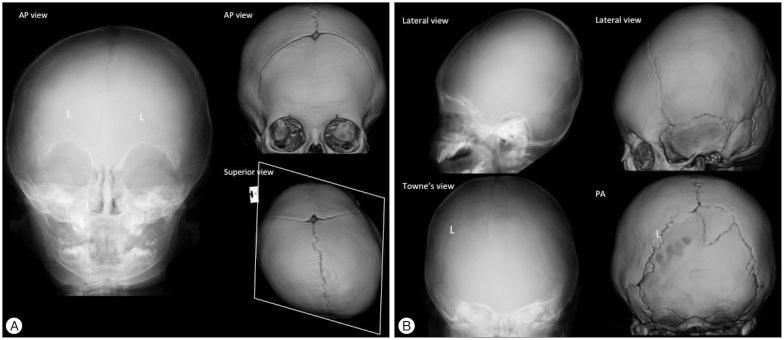

The purpose of this article is to review imaging findings and to discuss the optimal imaging methods for craniosynostosis. The discussion of imaging findings are focused on ultrasonography, plain radiography, magnetic resonance imaging and computed tomography with 3-dimensional reconstruction. We suggest a strategy for imaging work-up for the diagnosis, treatment planning and follow-up to minimize or avoid ionized radiation exposure to children by reviewing the current literature.

本文旨在回顾影像学表现,并讨论颅缝早闭的最佳影像学检查方法。影像学表现的讨论重点在于超声检查、X线平片、磁共振成像以及三维重建计算机断层扫描。通过回顾当前文献,我们提出了一种针对诊断、治疗规划及随访的影像学检查策略,以尽量减少或避免儿童受到电离辐射。